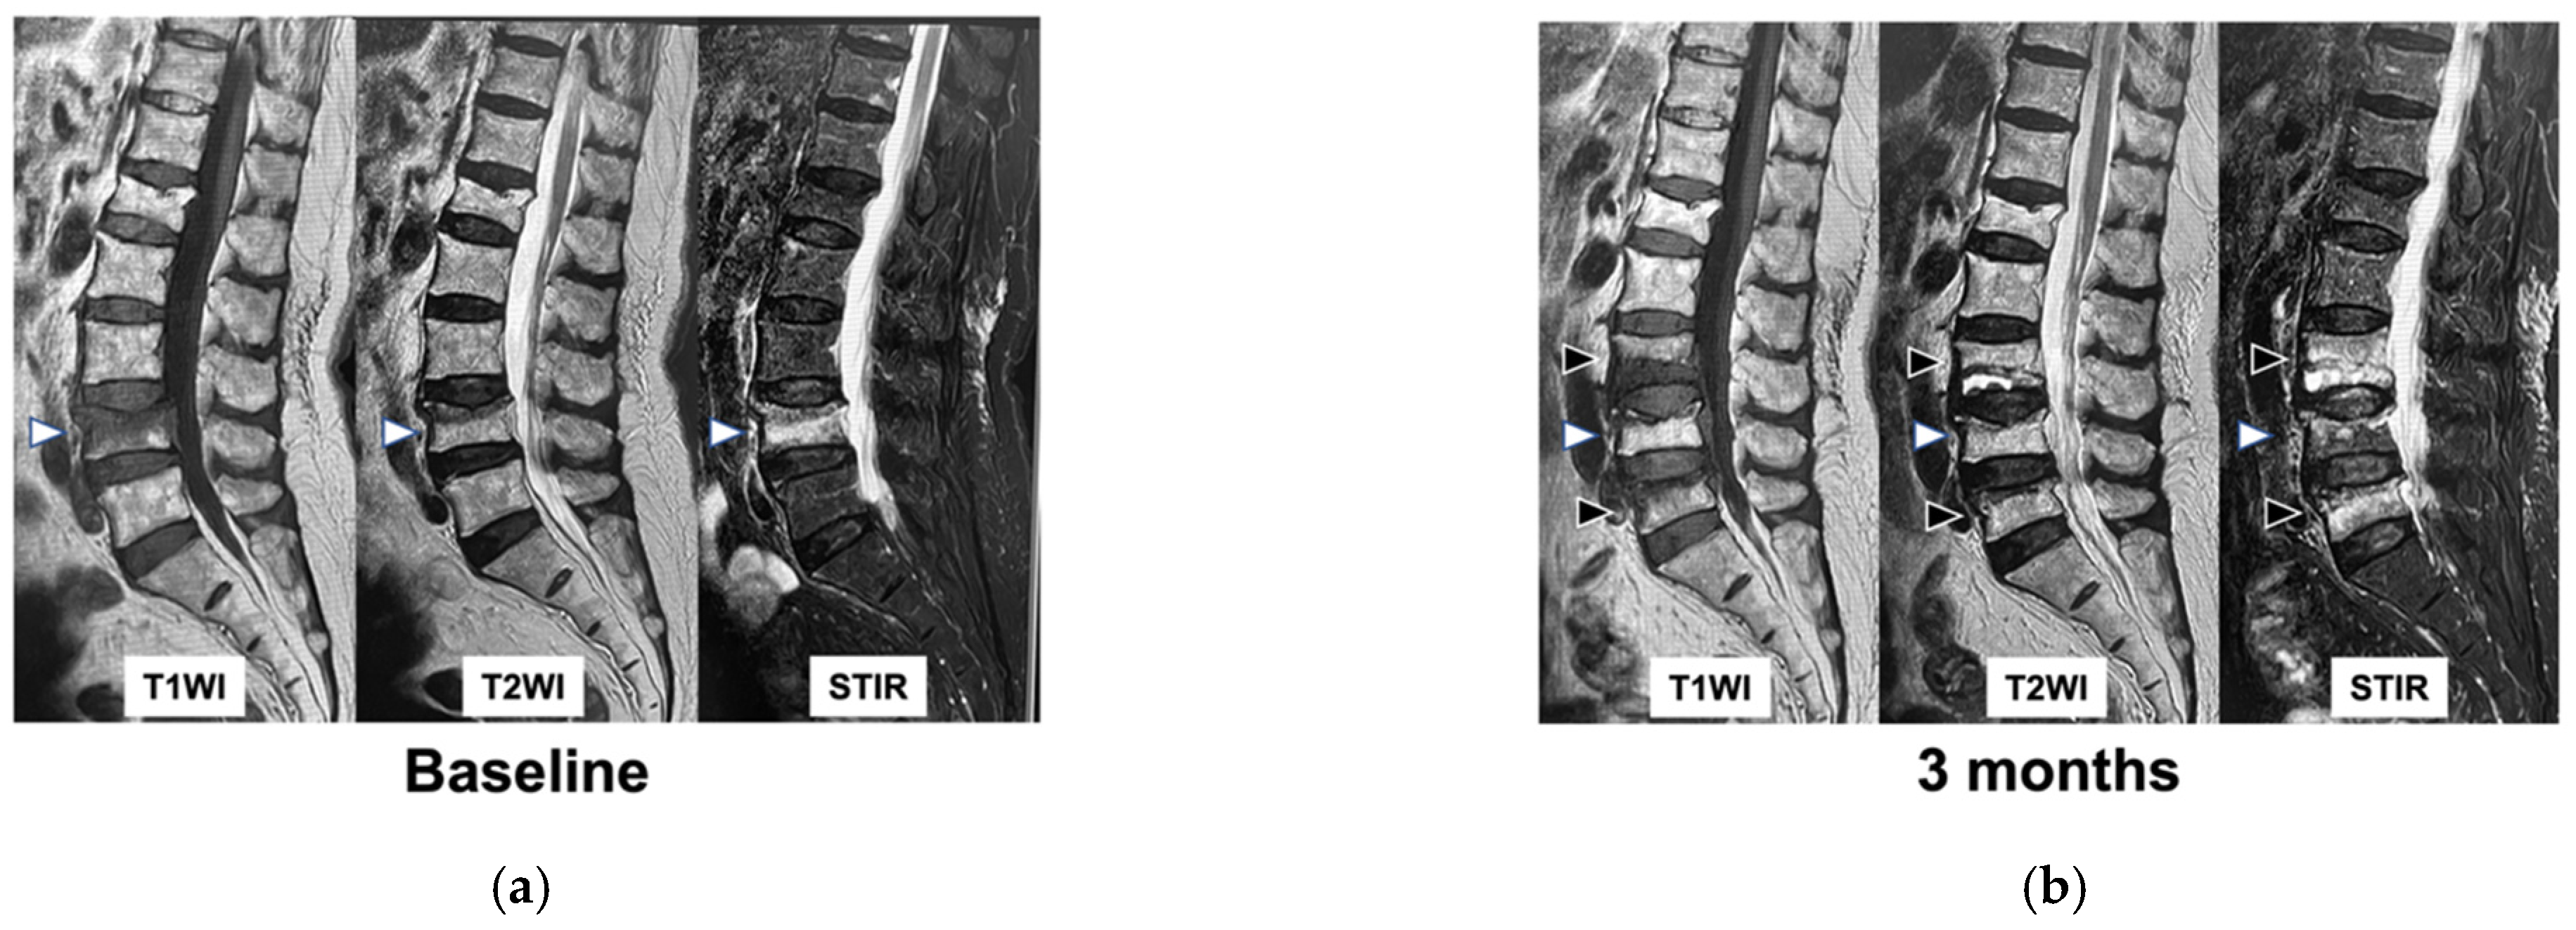

2.4. Imaging Assessment

- Takahashi, S.; Hoshino, M.; Takayama, K.; Iseki, K.; Sasaoka, R.; Tsujio, T.; Yasuda, H.; Sasaki, T.; Kanematsu, F.; Kono, H.; et al. Time course of osteoporotic vertebral fractures by magnetic resonance imaging using a simple classification: A multicenter prospective cohort study. Osteoporos. Int. 2017, 28, 473–482. [Google Scholar] [CrossRef]